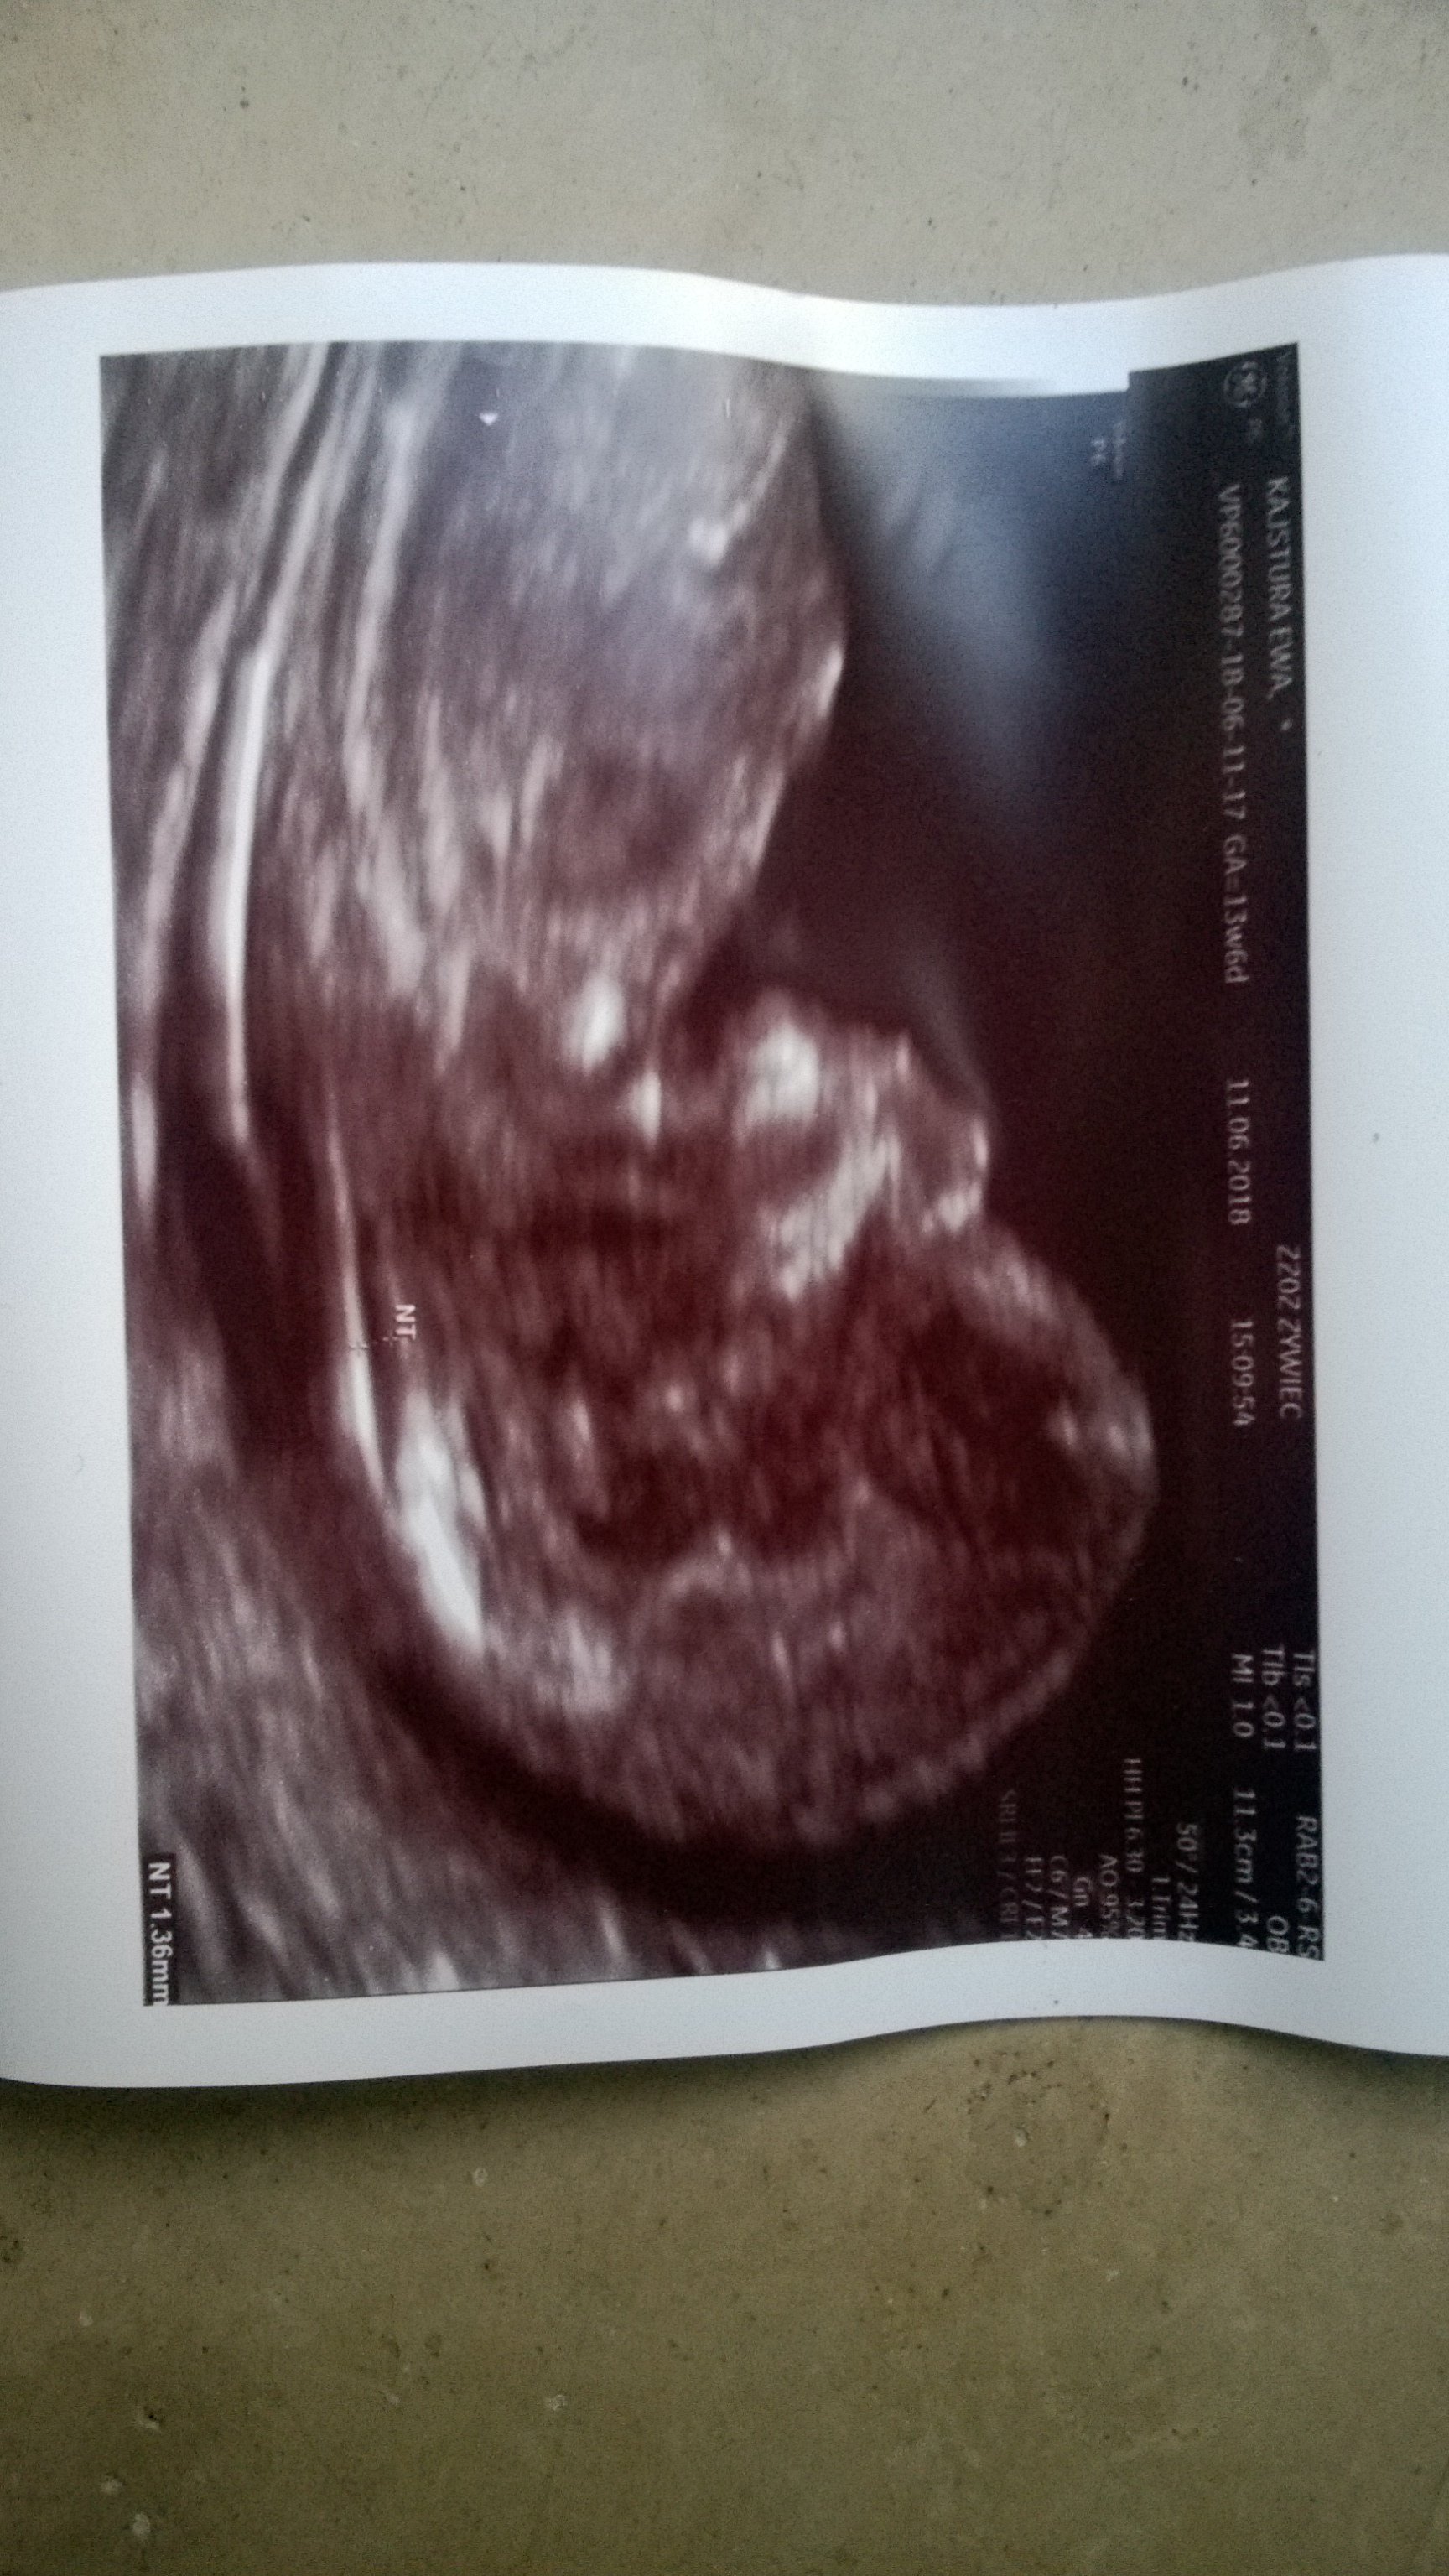

Dziś jest początek 14 tygodnia, wg usg jest 13t4d. Szczerze to nie wiem ile dzidziol ma cm, nie skupiłam się na tym, stresu miałam z tą przeziernoscia, a lekarka nie dała mi żadnego potwierdzenia z badania, tylko info że wyniki będą na wizycie, która za 3 tygodnie.Dzieki dziewczyny- w takim razie nie będę sie przejmować kierowniczka, moze sama niedoinformowana jest. Najwyżej za dwa tygodnie u lekarza zapytam o takie zaświadczenie.

Shiran który masz tydzien i jakiej wielkości jest dzidzius? Ja teraz w 13t6d mialam przyziernosc 1,3, dzidzi cos ponad 7cm (niestety nie dopatrzyłam dokladnie a na zdjęciu nie mam tego pomiaru) i lekarz mowil ze jest dobrze, ze przyziernosc powinna byc do 2mm. Według mnie możesz byc spokojna. A kość nosowa tylko lekarz ogladal i stwierdził ze prawidłowa.

Tak w ogóle moj dzidziuś z ostatniej wizyty

Zobacz załącznik 866857 Zobacz załącznik 866858 Zobacz załącznik 866859